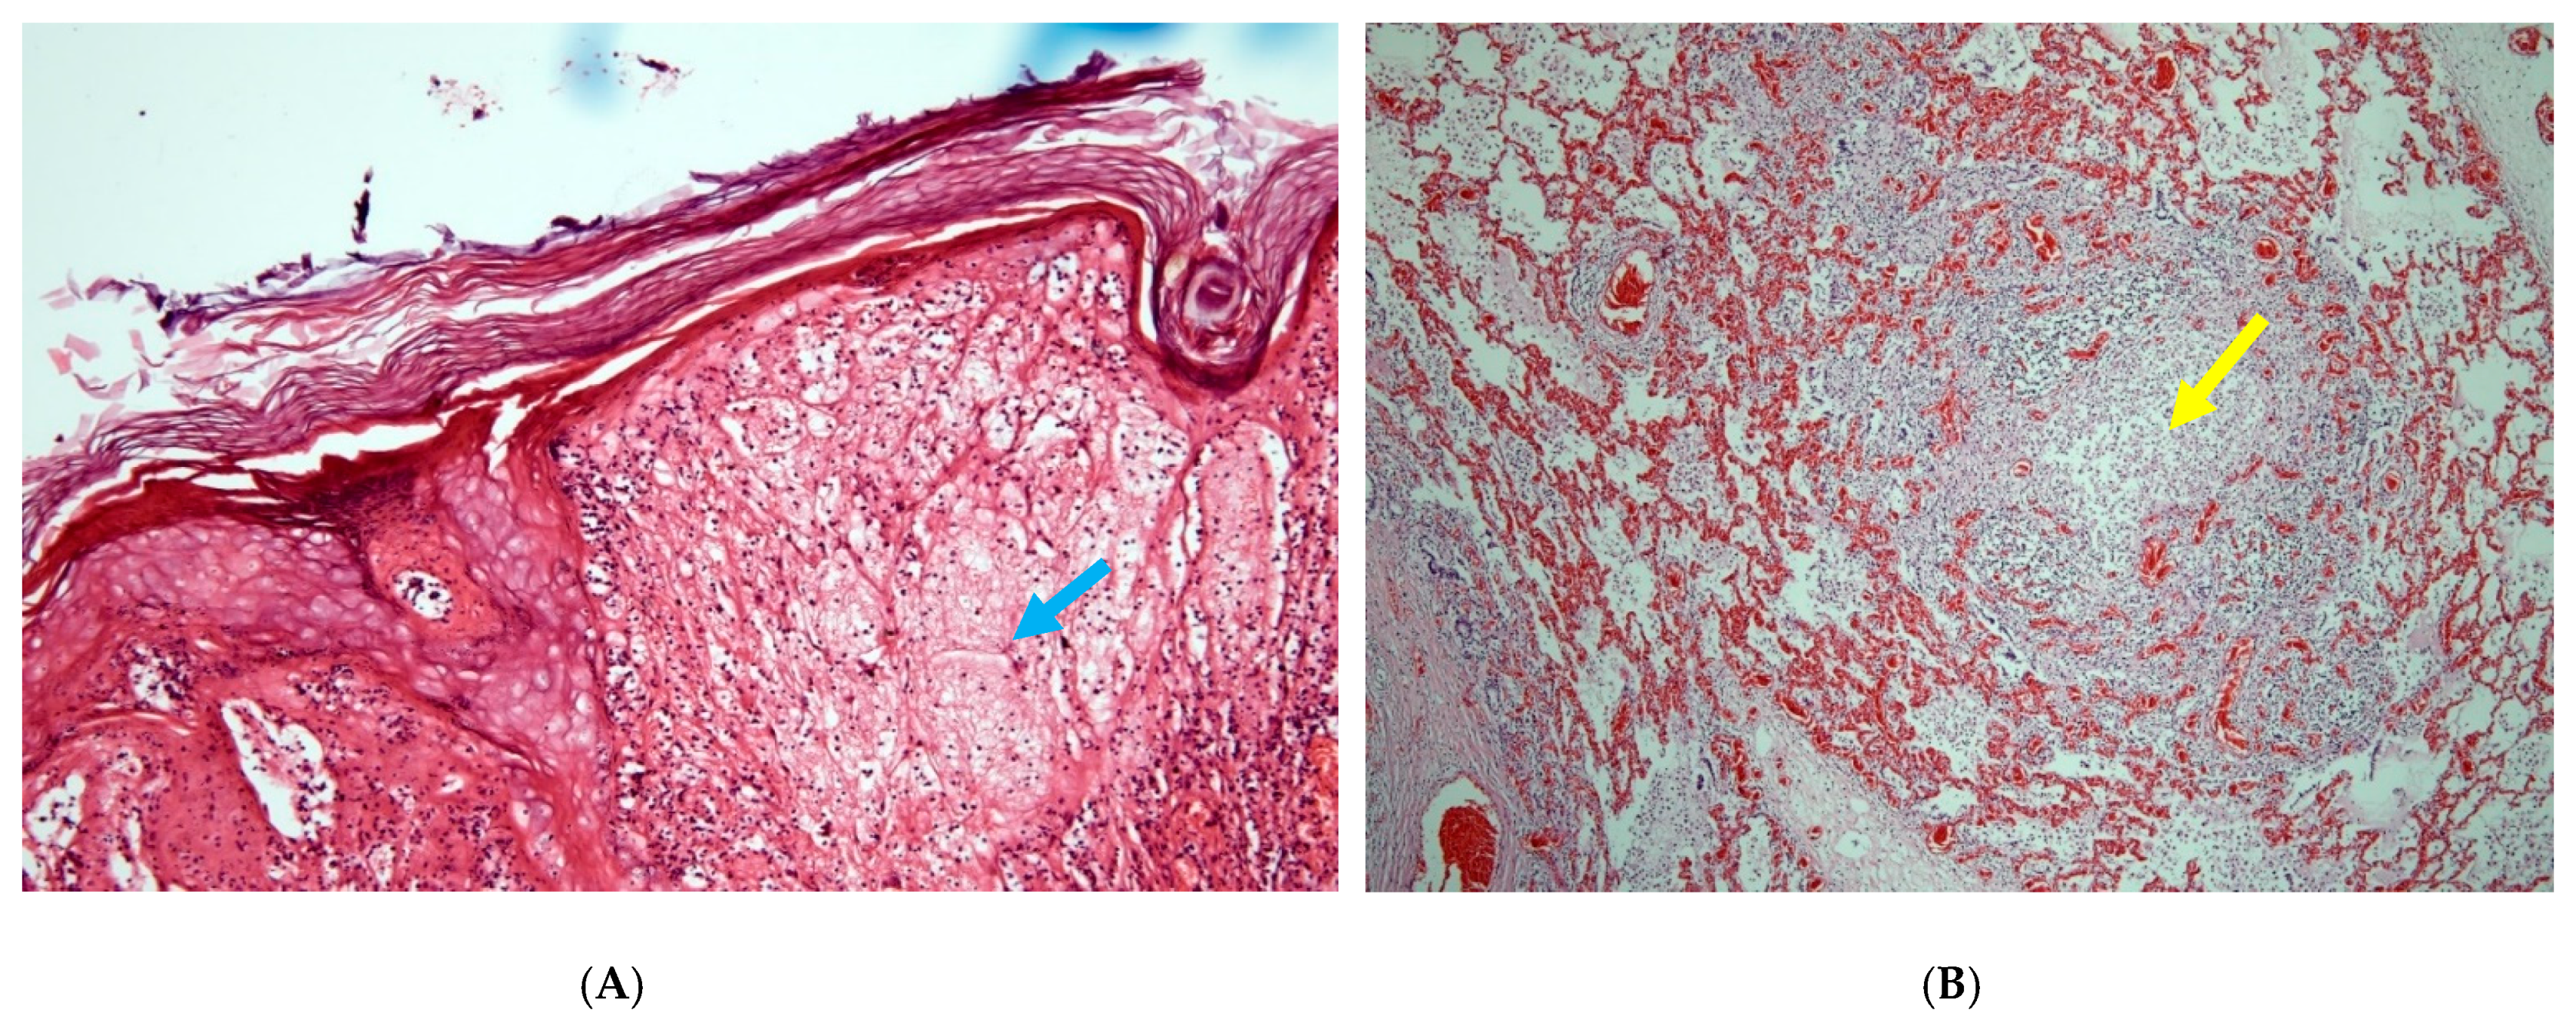

| 1 | D1621/20 Adult male | Legs, preputium, scrotum, nostril, lips | Gum, trachea, oesophagus, lung | Proliferative dermatitis, ballooning, pox-like inclusion bodies and pneumonia | Skin, body lymph nodes, trachea, oesophagus, gum and lung |

| 2 | D1734/20 Yearling female >2 years | Legs | Gum, trachea, oesophagus, lung | Proliferative dermatitis with bacterial infection | Skin, udder lymph nodes, lung, oesophagus |

| 3 | D1795/20 Yearling female >2 years | Pock nodules all over the body | Lung | Proliferative dermatitis, ballooning, bronchitis pox-like inclusion bodies, pneumonia | Skin, lung |

| 4 | D 1804/20 Yearling female >2 years | Pock nodules, especially in inguinal and perianal regions, swollen body lymph nodes, subcutaneous haemorrhages at the head | Lung | Proliferative dermatitis with pox-like inclusion bodies | Skin, body lymph nodes, trachea, tonsil, liver, spleen, brain, kidney, gum and lung |

| 5 | D2053/20 Calf male <1 year | Pock nodules all over the body | Mouth mucosa, gum, tongue, oesophagus, lung | Proliferative bronchitis, pox-like inclusion bodies | Skin, lips, nasal swabs, lung |

| 6 | D 1865/20 Adult female | Ventral abdomen/inguinal and perianal regions | Gum, trachea | Massive congestion and marked proliferation of follicular and parafollicular lymphatic tissue | Skin, gum, trachea, lung, liver |

| 7 | D2132/20 Adult female | Pock nodules all over the body | Lung, trachea | Proliferative dermatitis | Skin |